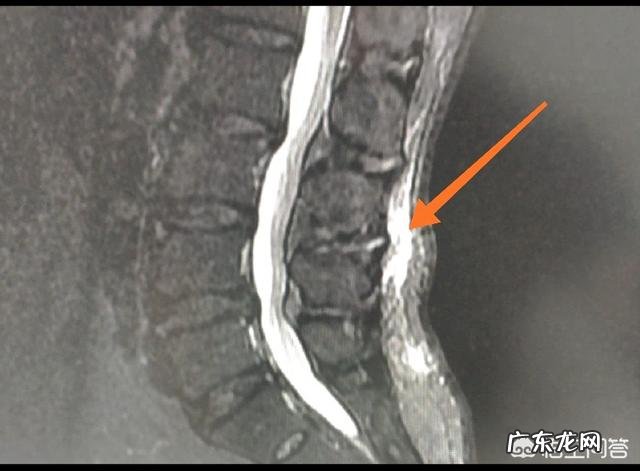

1、用力不当 , 拉伤:长时间的用力不当可能会导致后背肩胛部位的肌肉紧张 , 肌肉附着点发生慢性炎症 , 进而发生疼痛 , 这种疼痛多发生在一些需要进行搬运的工作人员 , 或者长期久坐的人 , 一般这种疼痛在热敷、休息后会有所缓解 。因用力不当导致的疼痛 , 大多可以在疼痛周围形成慢性炎症 , 比如下图的腰背部的浅筋膜炎 , 磁共振是可以看到的 。如果是应力性骨折那就要就诊脊柱外科 。